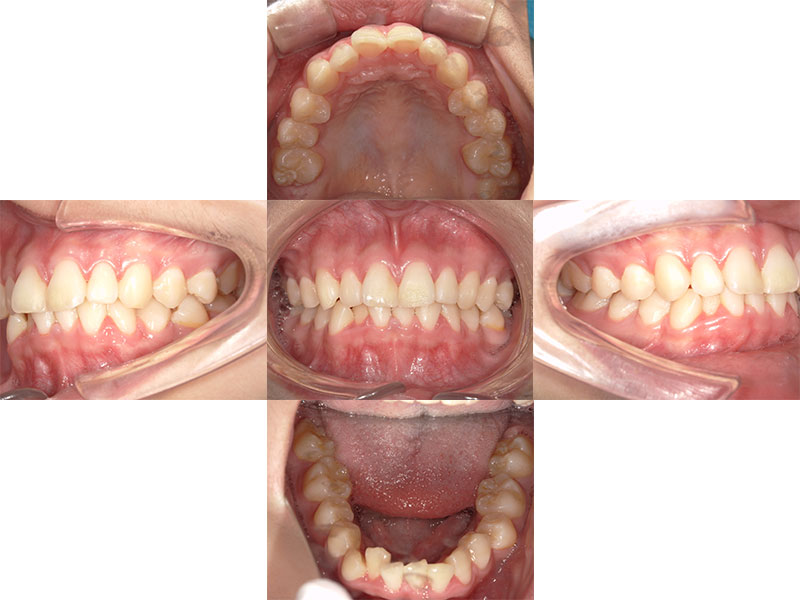

マウスピース矯正

治療前

Before

治療後

After

年齢 19

性別 女性

主訴 歯並びを治したい